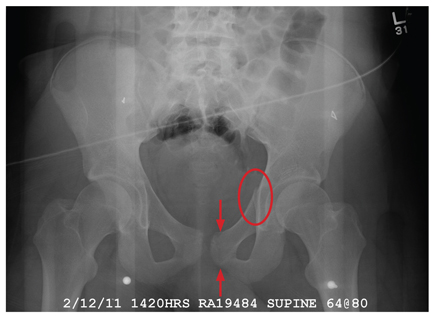

A 19-year-old man is transferred to your facility for injuries he sustained in a motor vehicle collision. He was an unrestrained passenger in a vehicle that went out of control and left the road. At the outside facility, he was found to have a chest injury and a pneumothorax, resulting in his transfer for tertiary level care. On arrival, he is complaining of some chest wall pain, but also states that his hips—especially the left one—are causing quite a bit of discomfort. His medical history is unremarkable except for sickle cell trait. Primary survey reveals stable vital signs and no obvious injury. On closer examination, with stress on his pelvis, he does complain of localized pain on the left side. Radiograph of the pelvis is obtained. What is your impression?

There is a cortical irregularity at the medial margin of the left iliac bone at the level of the acetabulum, strongly suggestive of a fracture. In addition, there may be a nondisplaced fracture within the superior/inferior rami on the left.

CT was recommended to further define these areas (and was already pending to evaluate the patient’s abdomen). Fortunately, there were no fractures within the hip joint, just the nondisplaced rami fracture.